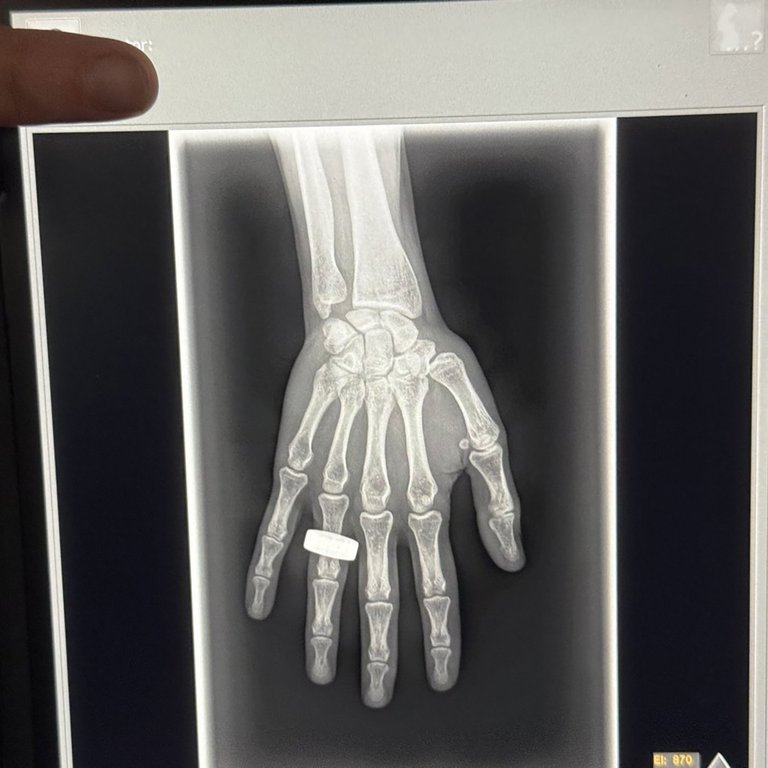

An x-ray of a hand taken at an unknown date. This is the first X-ray to be taken in space by KA Imaging of Waterloo, Ont. Four space tourists orbited the north and south poles earlier this month, a group of Canadians celebrated an X-ray image taken aboard the spacecraft using technology developed at the University of Waterloo.THE CANADIAN PRESS/HO KA Imaging **MANDATORY CREDIT**

Featuring a hand with a ring, KA Imaging says the image mirrored the first ever X-ray image accidentally captured over a century ago by Wilhelm Roentgen.

The X-ray was part of the SpaceXray project, one of the 22 scientific studies selected to be part of the mission.

Being able to do X-rays in space is a big deal, Karnick said. First, monitoring bone mineral density in astronauts is important due to the detrimental effect of microgravity, and the X-ray receiver the company produces is able to do that.

Karnick says the KA Imaging X-ray receiver, which is about the size of a large laptop, is also able to differentiate between bones and soft tissue such as the lungs or the heart, which could be useful for diagnosing pneumonia or cancers.

But before Wednesday’s hand image, Karnick says it wasn’t known if X-rays in space were feasible, due to concerns that natural background radiation from space might affect the quality of the image.

“The first images we’ve seen don’t seem to have any of those issues,” Karnick says.